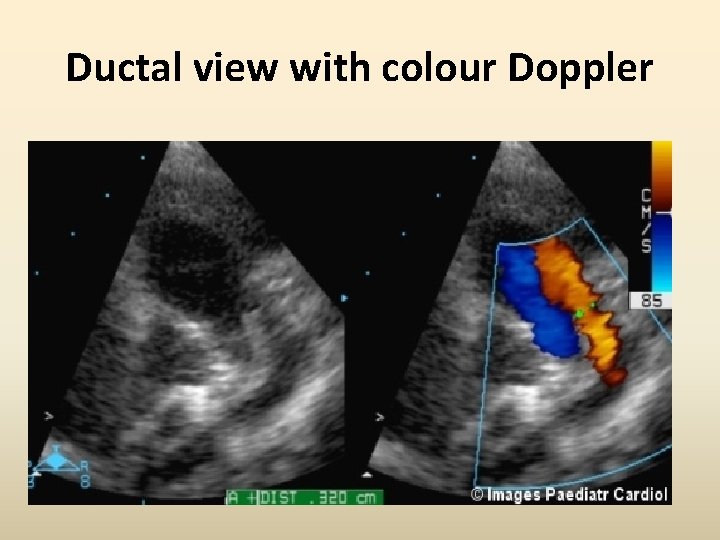

Ductal view with colour Doppler

Colour Doppler ductal diameter • Optimal gain settings (not too high) • Maximum Doppler scale settings • Duct should be imaged along its entire length Colour Doppler diameter > 2 mm ~ Qp/Qs >2: 1 in neonates Evans N, Iyer P. Assessment of ductus arteriosus shunt in preterm infants supported by mechanical ventilation: effect of interatrial shunting. J Pediatr. 1994; 125: 778– 785